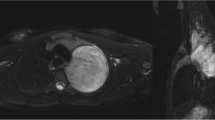

In this retrospective study, patients with BMs scanned with MRI between January 1, 2018, and December 31, 2021, were screened. Inclusion criteria were: (1) at least one sub-centimeter BM with an integer millimeter-longest diameter was noted in the MRI report; (2) patients were a minimum of 18 years of age; (3) patients with available pre-treatment three-dimensional T1-weighted spoiled gradient-echo MRI scan. The screening was terminated when there were 20 lesions in each group. Lesion volumes were measured with the help of intelligent automation software Jazz (AI Medical, Zollikon, Switzerland) by two readers. The Kruskal-Wallis test was used to compare volumetric differences.